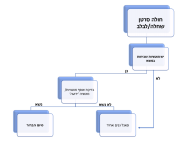

| 19:52, 18 בפברואר 2024 | חולה מעי-רחם-גידולי לינץ׳.png (קובץ) |  |

285 קילו־בייטים | Roeitul | 1 | |